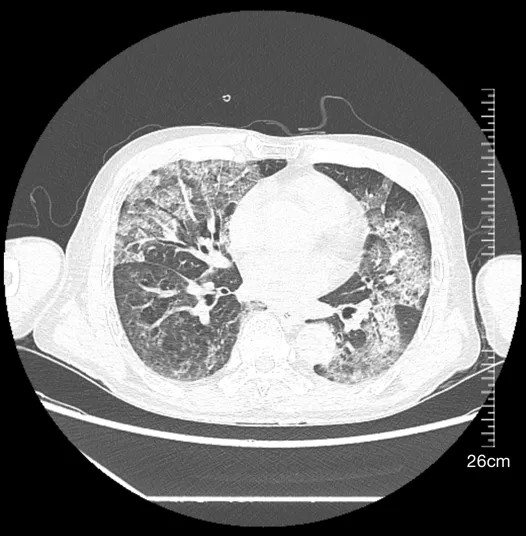

2024年6月10日肺部CT平掃影像

第二階段(2024年6月):轉(zhuǎn)診福州某三甲醫(yī)院后,肺炎快速進(jìn)展至雙肺間質(zhì)性改變,抗感染方案升級(jí)仍無效,激素治療一度緩解癥狀,肺部情況好轉(zhuǎn)后仍有進(jìn)食嗆咳,進(jìn)一步檢查發(fā)現(xiàn)急性腦干梗死。